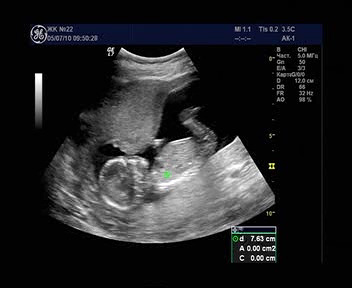

Об УЗИ: Первое УЗИ было ровно в 14 недель у замечательного узиста С.Г. Хачкурузова. Первые его слова были "О! .... (за эту коротенькую паузу мы с мужем многое успели передумать, в частности "Неужели двойня??")... девочка!"

.

Потом, в процессе обследования, спросил, как назовем. А имена у нас были приготовлены задолго до Б., для девочки - Майя. Вообще у меня мало слов находится, чтобы описать весь восторг и радость от первого УЗИ. Это был очень яркий момент в моей жизни!

Второе УЗИ мы проводили на 20-ой неделе там же, но узист был другой. Еще раз посмотрели на свою кроху, нам подтвердили девочку. Развивается хорошо:)

Третье УЗИ мы решили делать в нашей ЖК бесплатно. Назначили на 33-ей неделе, ждем. Очень надеюсь, что не ошиблись в этом решении и на качестве обследования это не сильно отразится.